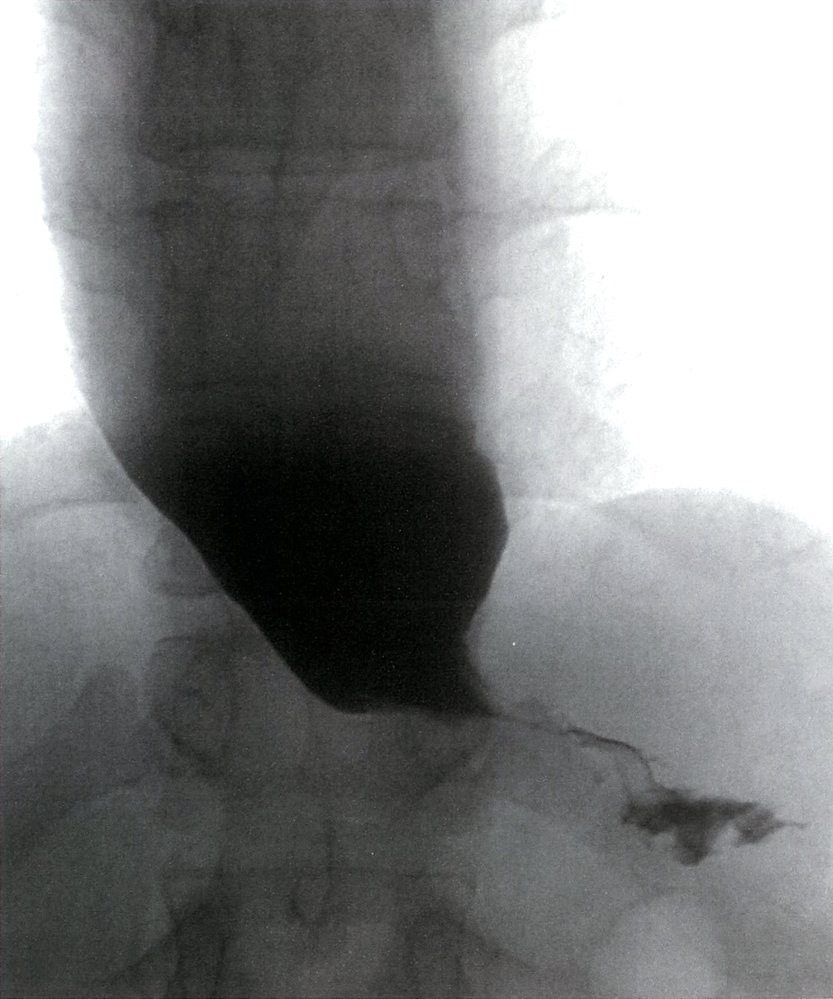

• Bird-beak sign: dilatation of the proximalesophagus with stenosis of the gastroesophageal junction

• Dilated esophagus that tapers distally (bird-beak sign/rat's tail appearance)

• LES spasm and delayed barium emptying